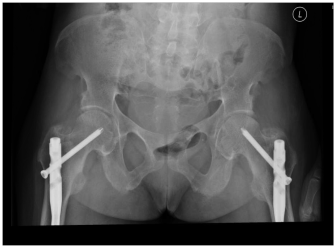

32-year-old African-American lady with history of rickets secondary to severe vitamin D deficiency since 3 years of age presented to emergency room (ER) with fatigue and severe carpo-pedal spasms. The patient had history of rickets and was on replacement with calcium carbonate and vitamin D. She was prescribed 50,000 units of vitamin D monthly by her primary care physician; however she was not adherent to the treatment regimen. Her past history included history of fracture at age 3 and a traumatic fracture of left femur at age 29, which required intramedullary rod placement with subsequent intramedullary rod placement on right side for fracture prevention (Figure1). Based on T score on DEXA scan (T-score not known as report was not available), she was diagnosed with osteoporosis and she received one dose of denosumab (60mg subcutaneous). Within 24 hours of administration of denosumab she developed, numbness and tingling along with spasms in both upper and lower extremities which worsened over the next day when she presented to the ER and was found to be severely hypocalcemic with an ionized calcium of 2.2mg/dL (4.7-5.3) and total calcium of 4.7 mg/dL (8.5-10.5). She had low magnesium of 1.1 mg/dL (1.7-2.7), phosphate of 2.7 mg/dL (2.5-4.8) and low 25 OH Vitamin D of 17 ng/mL (30-100) with elevated intact PTH levels of 428 pg/ml (12-72). Her 1,25 Dihydroxy vitamin D levels were 37.2 pg/mL (10-75).

Figure 1 X Ray Pelvis (Antero-posterior view) with bilateral intramedullary rod placement.